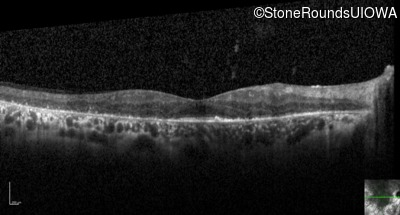

Optical Coherence Tomography - Left - 20/50

Exemplar / OCT Stack